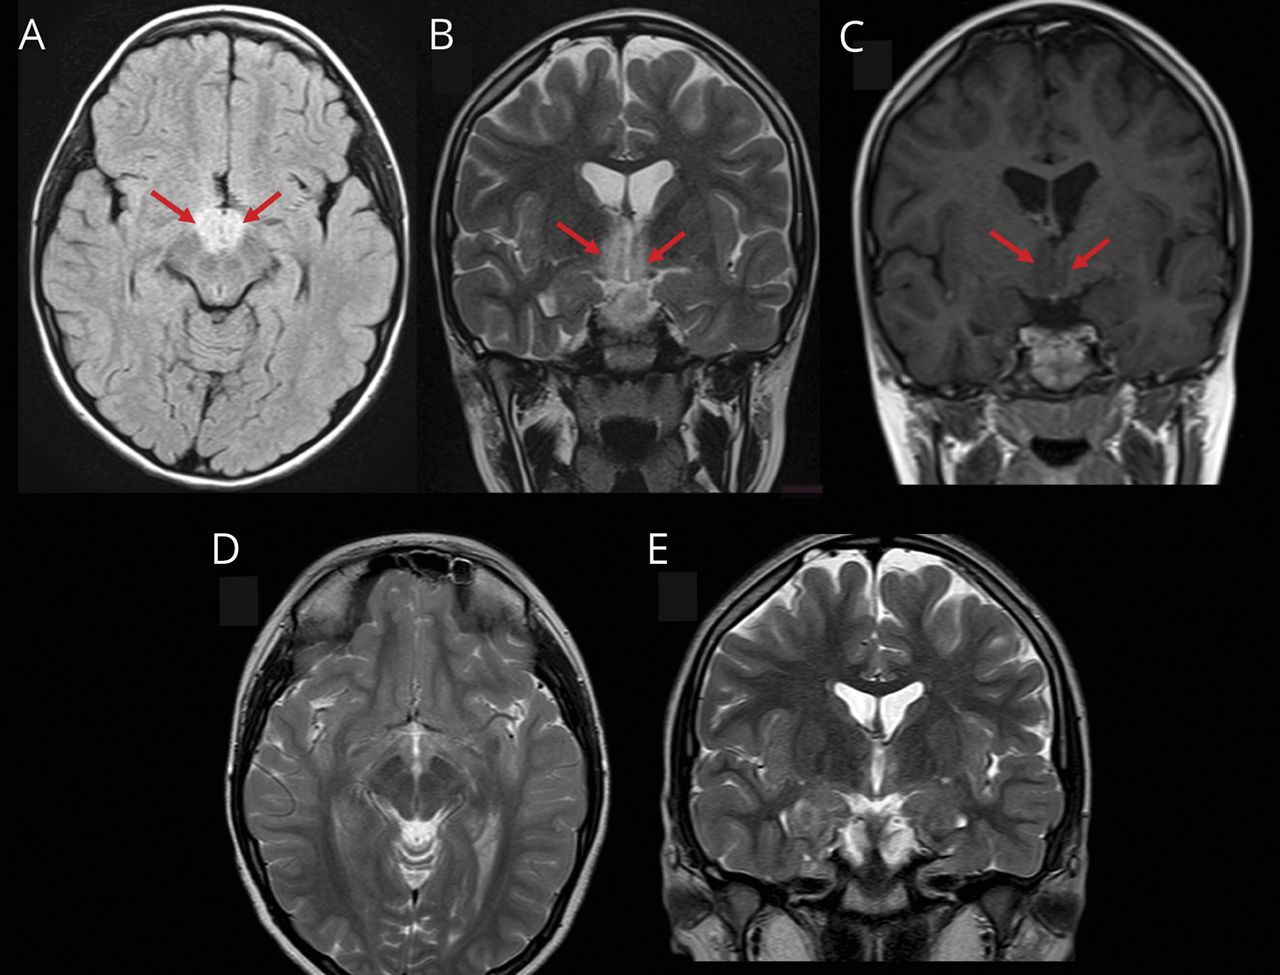

一名10岁女孩出现了15天的日间过度嗜睡和突然入睡、睡前幻觉、低食欲和行为改变的病史。脑部核磁共振检查显示双侧下丘脑病变(数字).我们发现血清中AQP4 -IgG抗体阳性,脑脊液中下丘脑泌素水平低(93 pg/mL)。诊断为继发于视神经脊髓炎谱系障碍的发作性睡病。服用糖皮质激素后病情好转。接受硫唑嘌呤免疫抑制维持治疗10个月后,随访神经影像学无新病变。任何间脑性临床综合征,如伴有下丘脑累及的嗜睡症,都应提示进行血清AQP4 -IgG检测。1,2

脑部核磁共振成像

症状2周后的脑MRI, (A)轴向液体衰减反转恢复成像和(B)冠状位t2加权图像显示双侧下丘脑高强度非强化病变(C)(箭头)。(D)和(E) t2加权图像显示诊断和治疗3个月后病变的分辨率。